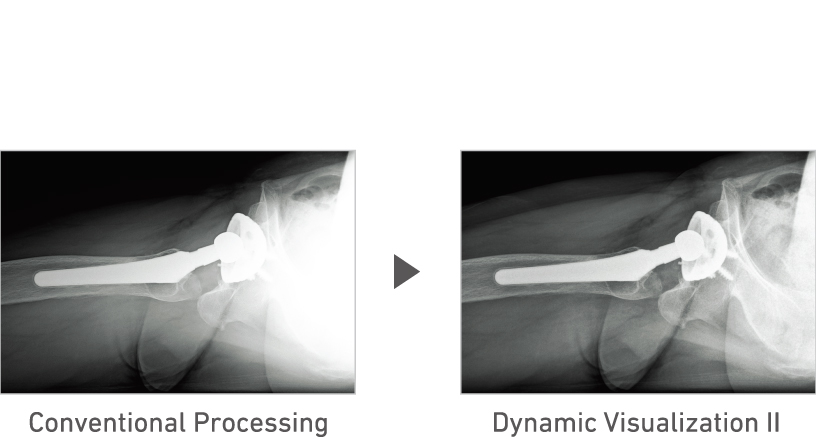

Advanced recognition algorithms automatically adjust contrast and density for individual body parts based on calculation of estimated 3D image data.*5